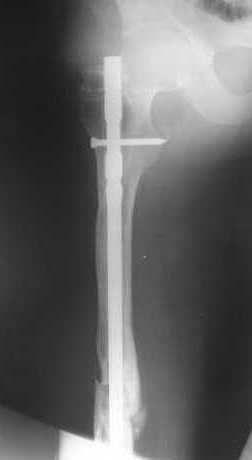

В приложении как раз видна эволюция использововшихся у нас большеберцовых гвоздей. Первый - дизайн как у UTN, второй - разнесены 45 градусные отверстия (зачем их вообще изначально так нелепо на одном уровне сделалм???), третий - убрано сиавшее лишним статическое отверстие, Herzog's bend перемещен более проксимально.

Забавненько смотрится... "век живи, век учись", как говорится. А чья мысль использовать блокируемые штифты для б/берцовой кости при переломах бедра? Такое встречалось где-то в литературе или это ваше ноу-хау?